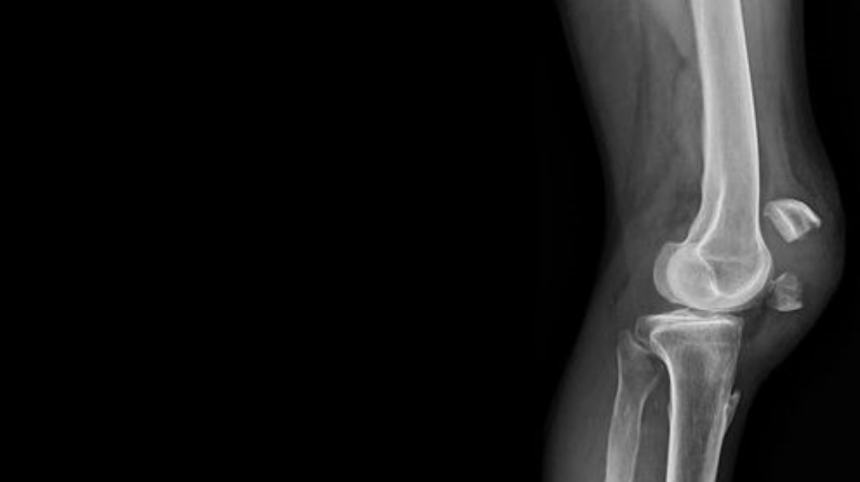

Toplumumuzda eklem rahatsızlıkları sıklıkla görülmektedir. Bunlardan bir tanesi de osteoartrittir. Osteoartrit tedavisinde birden fazla tedavi seçeneği mevcuttur. Non-steroid antienflamatuar ilaçlar (NSAİİ), kortikosteroidler, intraartiküler enjeksiyonlar ve fizik tedavi bu seçeneklerin başlıcalarıdır. İntraartiküler enjeksiyon hyalüronik asit, kolajen, kortikosteroidler ve salin kullanılarak yapılabilmektedir.

Bu zamana kadar yapılmış olan çalışmalarda çoğunlukla yüksek molekül ağırlıklı hyalüronik asit tercih edilmiş olup birer hafta arayla 30 mg/2mL olan çözeltiden 3 enjeksiyon yapılmıştır. Bu çalışmalar yapılırken diğer intraartiküler uygulama yöntemleriyle kıyaslanmıştır. Bazı çalışmalar, osteoartrite bağlı gelişen ağrı ve hasarın düzelmesinde anlamlı değerler elde etse de bazı çalışmalarda da anlamlı bir düzelme elde edilememiştir. Yapılan çalışmalarda seçilen hasta profili ve osteoartritin derecesi tedavinin sonuçlarında değişime sebep olmaktadır. Kişi bazlı bu değişiklikler tedavinin etkinliği konusunda şüpheye düşüren en önemli faktördür.

Tedavinin işe yaradığını gösteren çalışmalarda da intraartiküler kortikosteroid enjeksiyonu uygulamasıyla arasında anlamlı bir farklılık bulunamamıştır. Bu çalışmalarda intraartiküler kortikosteroid enjeksiyonunun hyalüronik asit enjeksiyonuna göre daha kısa sürede ağrı kesici etkinlikte olduğu gösterilmişse de uzun dönem iyileşme etkisi açısından hyalüronik asit enjeksiyonu daha avantajlı bulunmuştur. Fakat bu avantajlar arasında da anlamlı bir farklılık bulunmamaktadır. Maliyet etkin olması açısından bakıldığında ise kortikosteroid enjeksiyonu daha üstün gelmektedir.